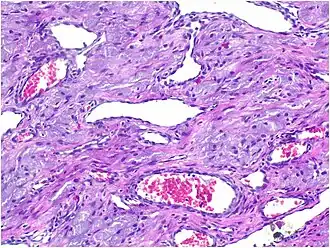

Histopathological Characteristics

Histopathologically, congenital epulis is usually characterized by the presence of big, rounded cells that fill the mucosa's lamina propria and have round to oval nuclei and an abundance of eosinophilic cytoplasm.[10] A thin layer of connective tissue separated the surface layer of cells from the growing new cells. Numerous histological traits, such as a fibrous and granulomatous appearance, have been reported in recent research.[10]

The pathophysiology of congenital epulis has been explained by several ideas. According to one such idea, some tumours have been demonstrated to spontaneously regress, and the tumor's growth ceases after delivery. This lends credence to the theory that hormones from the mother or foetus may influence its growth. Although it is still ambiguous, this lends credence to the theory that foetal or maternal hormones may contribute to its development. Furthermore, congenital epulis may have a mesenchymal origin, as indicated by ultrastructural and immunohistochemical results in documented cases, where the cells display characteristics of fibroblasts and histiocytes.[6]

These histopathological features are essential in distinguishing congenital epulis from other gingival and soft tissue neoplasms.

Immunohistochemical Analysis

Immunohistochemical staining serves as an important adjunct in the differential diagnosis of congenital epulis.[12] A key feature of congenital epulis is its lack of reaction to the S-100 protein test, which is typically positive in other similar tumors. When doctors examine the tissue using an S-100 stain, congenital epulis does not show a response, unlike other granular cell tumors. This distinction helps confirm the diagnosis and differentiates congenital epulis from other oral tumors in newborns.[6][13]